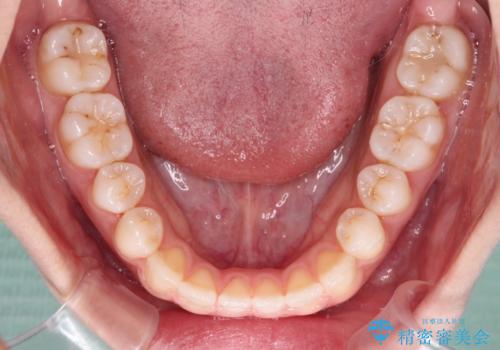

- 前歯の上下スペースと前歯の隙間を気にして来院された患者様です。

インビザラインにより上下の前歯の隙間を閉じていくこととしました。

上下の隙間に舌が入り込むことが、すきっ歯やオープンバイトの原因であったため、舌の筋肉のトレーニングも並行して行い、後戻りの抑制を図りました。